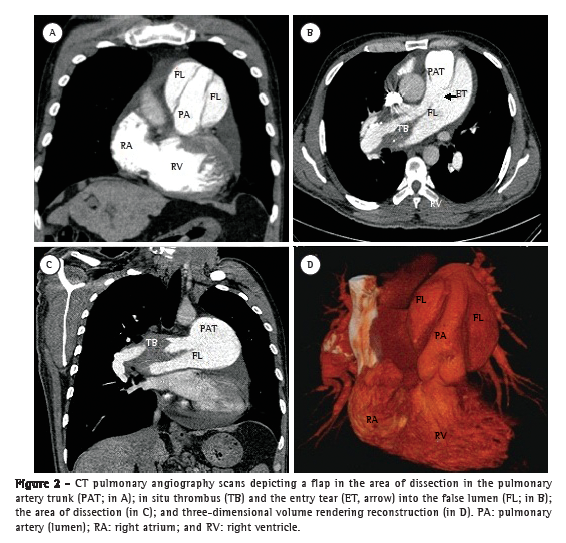

A 50-year-old male patient diagnosed four years prior with pulmonary hypertension related to schistosomiasis mansoni was admitted to the emergency room of the Federal University of Minas Gerais School of Medicine Hospital das Clínicas, located in the city of Belo Horizonte, Brazil. He presented with new onset, progressively worsening retrosternal chest pain and shortness of breath (functional class III pulmonary hypertension according to the World Health Organization). He had been diagnosed with chronic myeloid leukemia seven months prior and had since been on chemotherapy. At admission, transthoracic echocardiography revealed a large non-obstructive central thrombus in the right main pulmonary artery. The right atrium was dilated, and there was mild tricuspid regurgitation, with an estimated pulmonary artery systolic pressure of 63 mmHg. He was diagnosed as having in situ thrombosis as a complication of the long-standing pulmonary hypertension. After the possibility of acute coronary syndrome had been excluded, he was discharged on warfarin. He was re-admitted two months later due to progressively worsening, refractory chest pain. At that time, he had an SpO2 of 96%, and a third heart sound was audible at the lower left parasternal space, accompanied by a murmur of tricuspid regurgitation. The lungs were clear, and the peripheral arterial pulses were symmetric. Laboratory test results were unremarkable, including serum levels of creatine kinase, creatine kinase MB isoenzyme, and troponin. A resting electrocardiogram showed evidence of acute myocardial ischemia in the anterior leads. Transthoracic Doppler echocardiogram revealed a pulmonary artery systolic pressure of 62 mmHg, a thrombus in the right pulmonary artery, as in the previous examination, and the presence of a flap at that level that was compatible with pulmonary artery dissection (Figure 1). The diagnosis was confirmed by subsequent CT pulmonary angiography (CTPA; Figure 2). He was transferred to another cardiovascular treatment facility, where attempts were made to correct the defect with an endovascular procedure (via the femoral vein). During the perioperative period, the patient presented with refractory cardiogenic shock. Multiple efforts to resuscitate the patient were unsuccessful, and he died in the operating room.